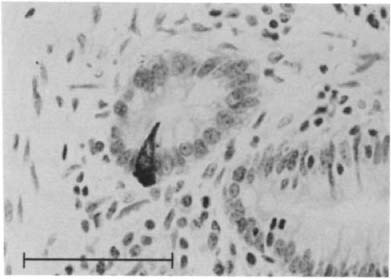

Figure 4. Figure 4.

Single somatostatin‐immunoreactive cell in epithelium of human duodenal mucosa, showing clear connection with lumen. Bouin's solution fixation; 5‐μm wax section; peroxidase antiperoxidase (PAP) immunostain, hematoxylin counterstain. Bar, 100 μm.